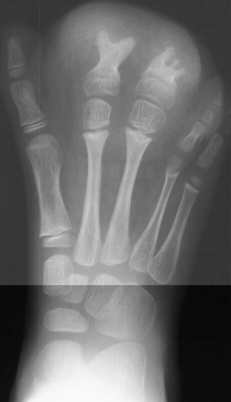

at age 5 years, she underwent partial amputation of the right

2nd and 3rd metatarsals(images 3 & 4). Now at age 10, she

has been doing well, participating in all sports. She has noted

that there has been some difficulty in finding shoes that fit,

but does not complain of any pain.